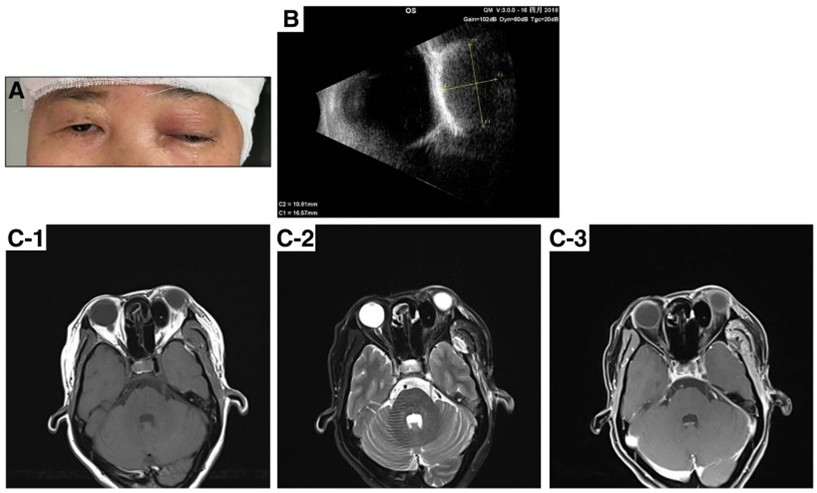

湘雅医院在2019年曾报道一个罕见的病例:一位51岁的患者因颅底脑膜瘤接受颅骨切除术,术中使用骨蜡封闭额窦。然而,如图1,患者术后3天出现左眼疼痛、肿胀、眼睑下垂及眼球突出的症状[4]。

图1 A. 患者左眼突出,眼睑下垂,眼睑肿胀;B. B超显示患者左眼眶有一椭圆形肿块,形状规则;C. 眼眶MRI示左侧眼眶上鼻侧低T1、T2信号团,呈规则椭圆形,未见强化,左侧视神经、上直肌、左眼球明显受压

影像学检查显示患者眼眶上鼻侧有一个规则、低密度的椭圆形肿块,明显压迫了左侧视神经、上直肌和左侧眼球。术后6个月,影像学检查显示骨蜡仍然占位挤压,患者眼球仍突出,视野无明显改善(图2)。